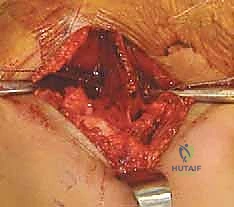

- الرد المفتوح (Open Reduction): إذا كان المفصل مخلوعاً بالكامل، يتم أولاً تنظيف التجويف الحُقي من أي أنسجة ليفية أو دهنية تعيق عودة رأس الفخذ، ثم يتم إرجاع رأس الفخذ إلى مكانه الطبيعي.

- القطع العظمي (The Osteotomy): يتم استخدام منشار جراحي دقيق أو أزاميل خاصة لإجراء قطع أفقي في عظم الحوض (فوق التجويف الحُقي مباشرة، من الشق الوركي الكبير إلى الشوكة الحرقفية الأمامية السفلية).

- إعادة التوجيه ووضع الطعم العظمي: يتم إمالة التجويف الحُقي للأسفل والأمام. وللحفاظ على هذا الوضع الجديد، يتم أخذ قطعة عظمية مثلثة الشكل (طعم عظمي - Bone Graft) من الجزء العلوي من عظم الحوض، ويتم حشرها في مساحة القطع العظمي كـ "وتد".